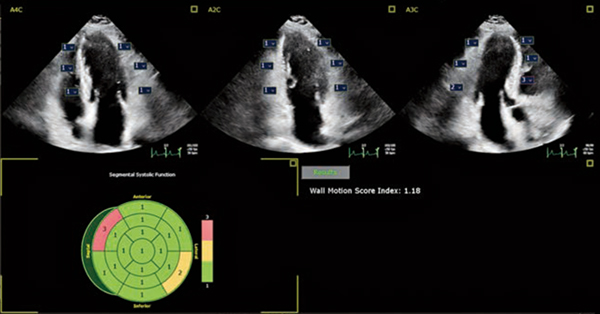

Auto SWMは,strainやvelocity,displacementなどの指標を考慮し,17セグメントの局所壁運動異常を1:Normal,2:Hypokinetic,3:Akinetic(Dyskinetic,Aneurismalも含む)の3つに分類し,自動的にブルズアイ表示する(図2)。従来,局所壁運動異常の評価は,検者の主観によるところが大きく,バラツキを低減するためにも検者間で目合わせを行うことが重要とされていた。Auto SWMを使用することで,経験の浅い検者へのトレーニングツールとして,さらに,検者間誤差の低減に役立つ可能性もある2)。

図2 Auto SWM

AIにより局所壁運動異常がブルズアイ表示される。